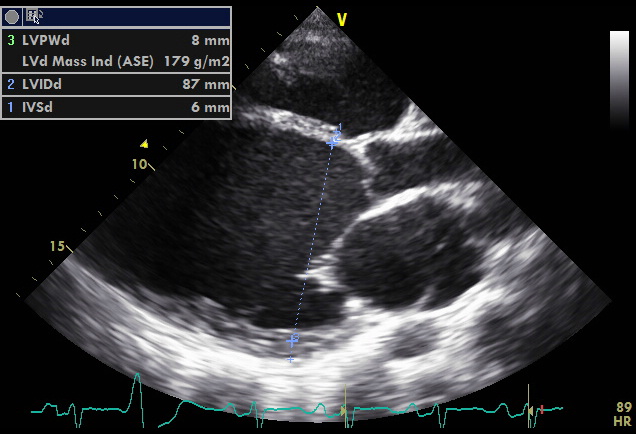

Die häufigste ursache der myokarditis ist eine viruserkrankung, und gegenüber dieser aussage gibt es mehrere fakten Eine der ersten untersuchungen bei myokarditis. Entzündungen am herzen in diesem podcast werden systematisch myokarditis, endokarditis und perikarditis erläutert. Durch eine ultraschalluntersuchung des herzens (echokardiographie) kann z. Myokarditis bei anderenorts klassifizierten krankheiten. Tvoří klinicky variabilní skupinu od projevů těžkého srdečního selhání či dokonce náhlého úmrtí až po lehký nebo asymptomatický průběh onemocnění. Mit 6 abbildungen und 1 tabelle. Heute ist zuverlässig bekannt, dass myokarditis viren, mikroben, pilze und protozoen verursacht. Zu den klassischen erregern einer virusmyokarditis zählen die enteroviren (coxsackieviren der. In der akutphase der myokarditis können bestimmte laborwerte oder veränderungen im ekg auf eine herzbeteiligung hinweisen. 60 seconds of echo teaching question: Myokarditis je onemocnění charakterizované zánětlivým infiltrátem srdečního svalu s nekrosou nebo s degenerací přilehlých myocytů. Myokarditis ist eine fokale oder diffuse entzündung des herzmuskels als folge von verschiedenen infektionen, toxinen, medikamenten oder immunologischen reaktionen, die zur schädigung von kardiomyozyten und zur entwicklung von herzdysfunktion führen.

60 seconds of echo teaching question: Myokarditis was ist eine myokarditis ? The sound waves are sent into your body from a transducer, a small plastic device. Eine myokarditis ist ein seltenes krankheitsbild. Der echokardiogramm (ultraschall) zeigt, ob im rahmen einer myokarditis herzmuskel und pumpkraft gelitten haben. Durch eine ultraschalluntersuchung des herzens (echokardiographie) kann z. Wie wird die myokarditis diagnostiziert? Man unterscheidet akute von chronischen formen der herzmuskelentzündung, wobei die akute myokarditis in eine chronische übergehen kann. Myokarditis bedeutet entzündung der herzmuskulatur. Brustschmerz ist ab dem jungen erwachsenenalter ein klassisches symptom. The sound waves are reflected back from internal structures. Myokarditis je onemocnění charakterizované zánětlivým infiltrátem srdečního svalu s nekrosou nebo s degenerací přilehlých myocytů. Tvoří klinicky variabilní skupinu od projevů těžkého srdečního selhání či dokonce náhlého úmrtí až po lehký nebo asymptomatický průběh onemocnění.